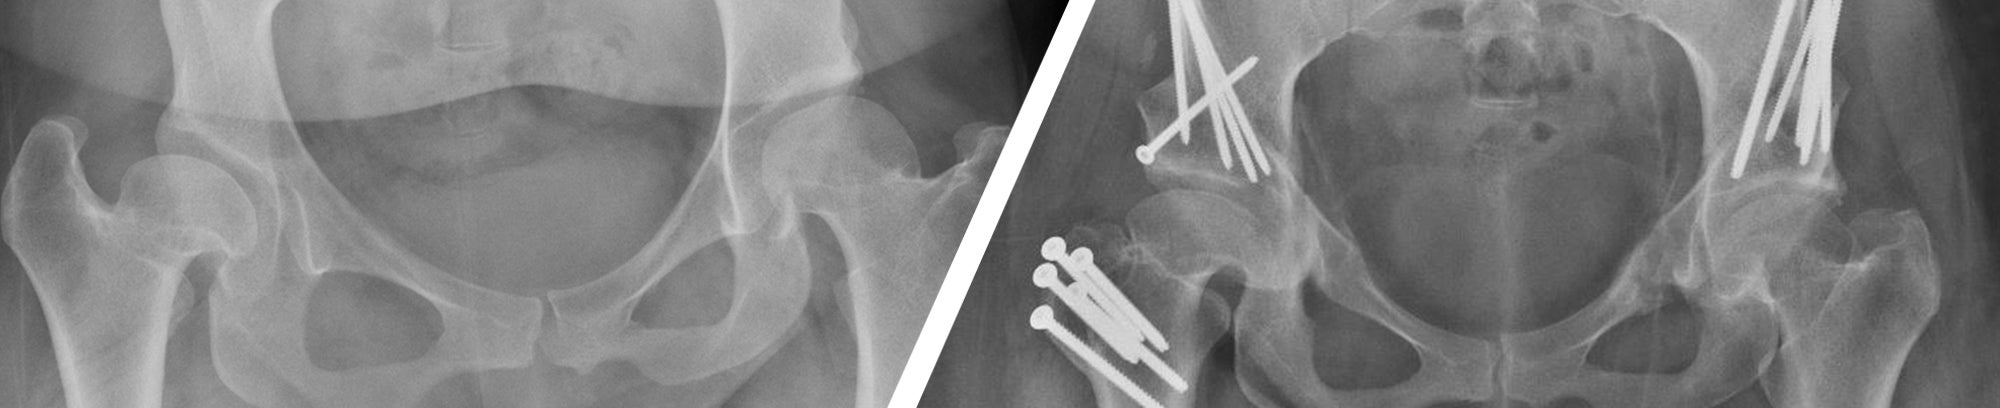

Valley Children’s Orthopaedic Center houses the first Hip Program for infants and children, and adolescent and young adults up to 35 years of age in the Central Valley. Our program specializes in the diagnosis and treatment of all pediatric through young adult hip disorders.

We provide a wide range of treatment options for both common and complex hip disorders. We treat infants and children with congenital, developmental and post-traumatic hip disorders with access to cutting edge intervention without having to travel outside of the Valley.

Valley Children’s orthopaedic specialists treat a wide variety of hip abnormalities in teens and young adults up to 35 years of age. Common and complex hip conditions can often go undetected in early childhood and may not be diagnosed until chronic hip pain or other symptoms begin to occur during adolescence and young adulthood. Our nationally recognized hip preservation specialists provide treatment from early intervention to prevent further joint damage, to complex surgical intervention to reduce pain and improve function.